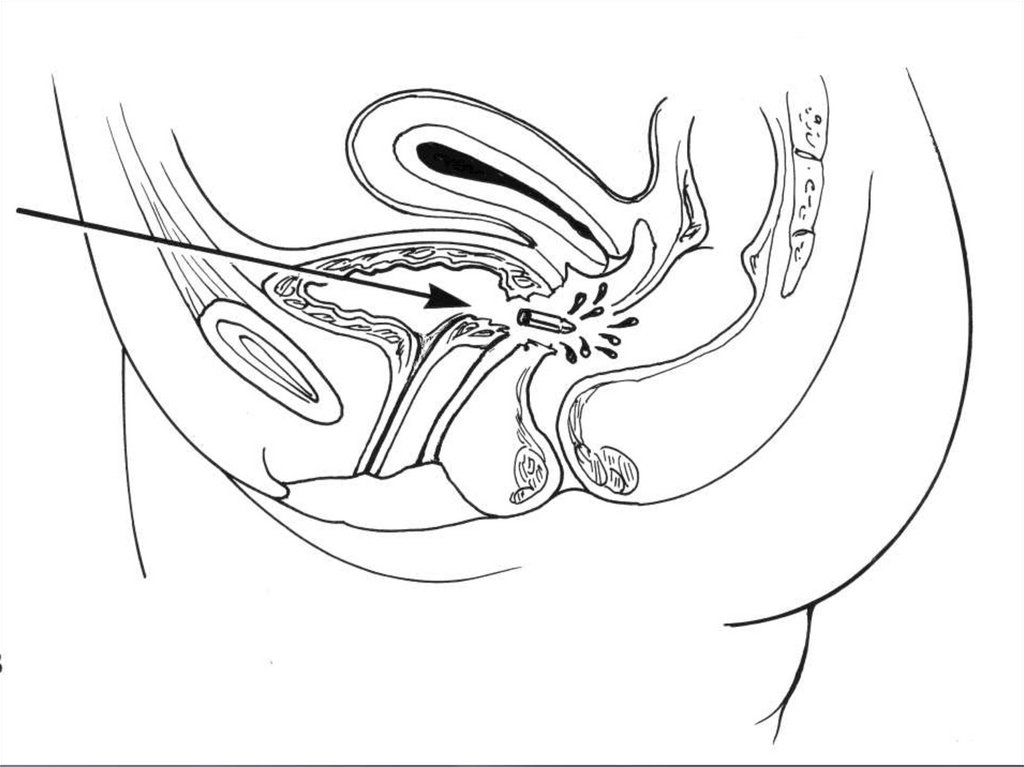

70. Механизмы травмы

Внебрюшинные разрывы, как правило,

сочетаются с повреждением костей

таза

Возникают за счет разрыва связочного

аппарата или повреждения мочевого

пузыря костными отломками.

71. Механизмы травмы

Внутрибрюшинные разрывы обусловлены

резким повышением внутрипузырного давления

при наполненном мочевом пузыре

Чаще происходят в области верхушки («слабое

место»)

Имеет значение состояние стенки мочевого

пузыря до получения травмы